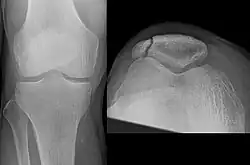

The patella can break in various ways depending on the way it is injured, and into two or more pieces.[1] Types include transverse, the most common, with one fracture line;[5] marginal; osteochondral; and the rare vertical type, or stellate, where a direct compression force gives rise to a comminuted pattern.[5][7] Patella fractures can be further classified as displaced, where the broken ends of bone do not line up correctly and separate by more than 2mm, or undisplaced and stable where pieces of bone remain in contact with each other.[1][7] If fragments of patella bone stick out from the skin it is known as an open patella fracture, and closed if the overlying skin is intact.[1]

Transverse fracture of patella -

Comminuted fracture of patella -

Osteochondral fracture of patella -

Vertical patella fracture